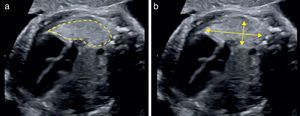

Para el cálculo del LHR O/E, debe seguirse el protocolo descrito en la tabla 2 pudiendo utilizarse la medición tanto de los diámetros máximos como del trazado del contorno pulmonar (fig. 2).

Protocolo de medición del LHR O/E

| El pulmón contralateral a la HDC debe quedar próximo a la sonda |

| Obtener corte axial del tórax a nivel de 4 cámaras cardíacas |

| Evitar la sombra producida por las costillas |

| Magnificar la imagen hasta que el tórax fetal ocupe toda la pantalla |

| Ubicar los marcadores, o calipers, de acuerdo con el método de medición del área pulmonar |

| División del área pulmonar por la CC (mm) para obtener LHR |

| Dividir el LHR obtenido por LHR esperado para la EG para obtener el LHR O/E |

Hemos descrito la curva de aprendizaje para lograr una buena competencia en la medición del LHR, que incluye la realización de 77 exploraciones24 siguiendo el protocolo de medición descrito previamente.